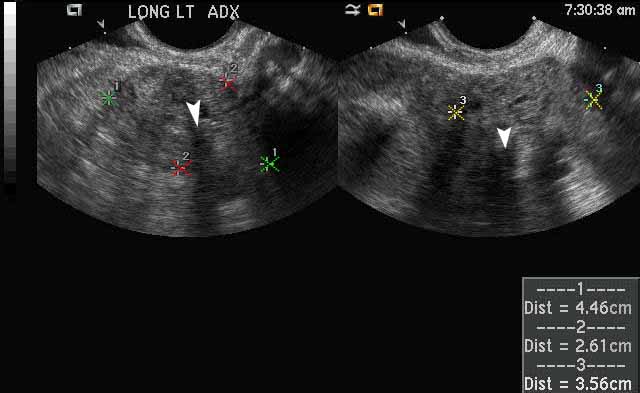

Dermoid Imaging

Dermoid

Image 1

The large right adnexal dermoid cyst depicted in this image between the red calipers has both fat and fluid components, which is a classic finding. The white x’s demarcate the hypochoic, or dark, fluid components of the cyst and the black x’s demarcate the echogenic, or white, fat components of the cyst. |